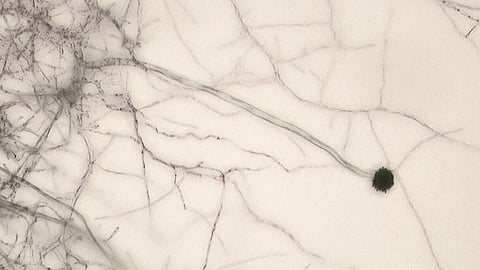

Aspergillus, a genus of fungi commonly found in the environment, has become a significant health concern due to its potential to cause aspergillosis—a range of illnesses affecting the respiratory system. Individuals with compromised immune systems, such as those undergoing chemotherapy, organ transplant recipients, or patients with chronic lung diseases, are particularly vulnerable to these infections.

The study utilized climate models to assess how three species—A. fumigatus, A. flavus, and A. niger—might migrate into regions like North America, Europe, China, and Russia under various warming scenarios. A. fumigatus, which thrives in temperate climates, and A. flavus and A. niger, favoring warmer conditions, are expected to see significant range expansions.